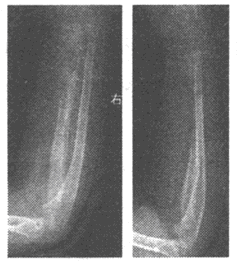

4、单项选择题

男,7岁,右前臂肿痛20天,发病时皮温较高,体温达39℃。实验室检查:WBC:12.05×109/L,中性粒细胞79%。右尺桡骨正侧位DR片如图

最可能的诊断是()

E.化脓性骨髓炎